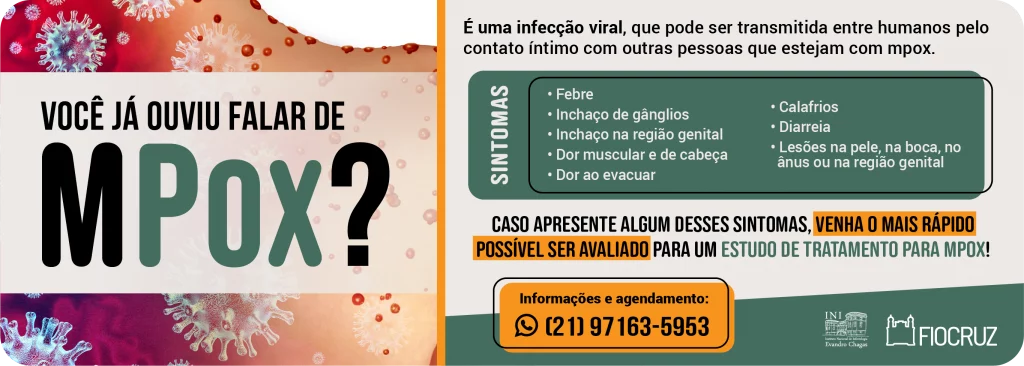

“Cozinhando com PrEPina Blue”, 2º episódio (mpox), com as especialistas do INI/Fiocruz, Valdiléa Veloso, Beatriz Grinsztejn e Mayara Secco, janeiro de 2025.